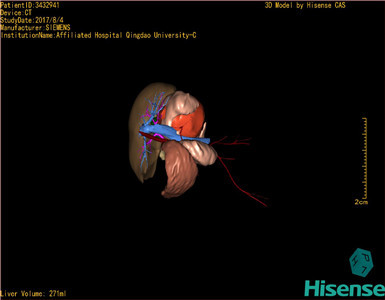

术前三维重建及手术方案设计:

将0.625mm双源薄层CT资料的静脉期和动脉期Dicom格式文件导入海信CAS系统。

通过调节窗宽窗位调整CT序号,对肿瘤,肝实质,胆囊,下腔静脉,肿瘤,肝动脉、门静脉及肝静脉等进行三维重建;系统自动计算肿瘤体积和肝脏体积。

模拟手术操作,自动计算切除肿瘤体积。肝脏体积为271ml,通过术前模拟手术,精准判断手术可行性。

术前三维重建:

重建图片